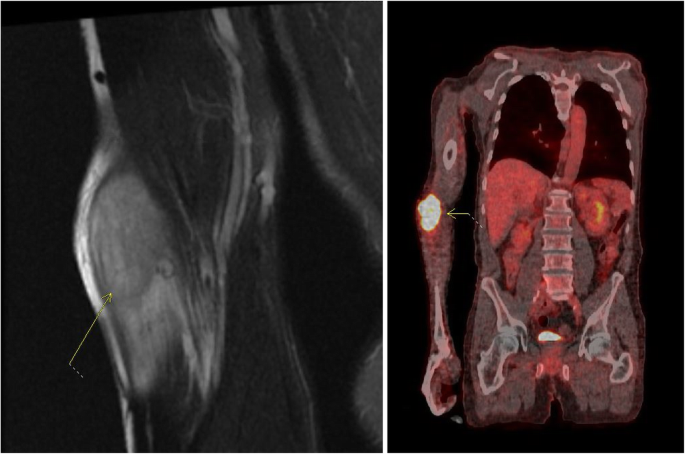

According to NCCN guidelines, surveillance was planned with a history and physical exam every 3–6 months for the first 2 years, and every 6–12 months for the subsequent 3 years, and finally annually thereafter. Surveillance imaging was also planned according to NCCN guidelines with a contrast CT chest, abdomen, and pelvis every 6–12 months for the first 2 years and then annually for 5 years [39]. Approximately 3 months after surgery, the patient developed a rapidly enlarging right lateral forearm mass. MRI revealed a 7-cm heterogeneously enhancing intramuscular mass within the brachioradialis muscle. This mass was found to be FDG avid on PET (SUV 12) and several right axillary lymph nodes were noted to have mild uptake with SUV 2.9 (Fig. 4). Core biopsy revealed poorly differentiated adenocarcinoma, consistent with metastasis from his gastric primary. We discussed with the patient that resection of this mass would not improve his survival and that extremity metastasis has shown to be a poor prognostic sign in the literature [37]. Next generation sequencing was performed on this extremity metastasis, which included a gene profile of at least 500 genes. This was positive for PDL1, suggesting a benefit from immunotherapy. Positive PDL1 was defined by a Combined Positive Score, which is calculated by the number of PDL1 staining cells divided by the total viable tumor cells multiplied by 100. Somatic mutations were also noted in MSH2, MSH6, and PDL1 and were negative in HER2. However, genetic testing revealed no germline mutations such that a diagnosis of Lynch syndrome was not supported. Our recommendation was to initiate systemic therapy with a PDL1 inhibitor (pembroluzimab) prior to resection of this metastasis as a means to evaluate the tumor response to treatment. However, the patient strongly desired upfront resection of the tumor as it was symptomatic, so a successful metastasectomy was performed. Surveillance was continued with a thorough physical examination and PET scan every 3 to 6 months. Surveillance PET scans showed response to immunotherapy with resolution of the FDG avidity in his right axilla, as well as a decrease in the size of the previously FDG avid right axillary node (Fig. 5). EGD performed at 11 months following initial resection did not demonstrate any signs of local tumor recurrence at the esophagojejunostomy anastomosis (Fig. 6). The patient remains disease free at the time of this publication, 20 months from the time of diagnosis and 1 year after the diagnosis of metastatic disease.